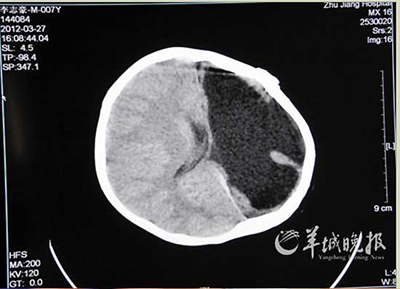

CT顯示小豪只有右腦

男童小豪出生滿月時(shí)因意外受傷導(dǎo)致大腦受損,左腦極度萎縮變形,且患上癲癇。這個(gè)不幸的孩子卻對(duì)音樂有極大的興趣與天賦,被稱為“半腦神童”。近日,珠江醫(yī)院切除小豪壞死的左腦,去除了癲癇的病灶。

癲癇病治療專家們對(duì)小豪進(jìn)行了詳細(xì)的檢查和會(huì)診。他們發(fā)現(xiàn),小豪的左腦因?yàn)橛讜r(shí)的創(chuàng)傷,早已萎縮變形,不過腦電波檢查卻發(fā)現(xiàn),引起癲癇放電的腦電波主要從右腦發(fā)出,這一點(diǎn)使醫(yī)生們有點(diǎn)疑惑,因?yàn)檫@與一般的癲癇發(fā)病情況正好相反。

經(jīng)過近9個(gè)小時(shí)的手術(shù),醫(yī)生完整地切除了小豪的左腦,他成為名副其實(shí)的“半腦人”。